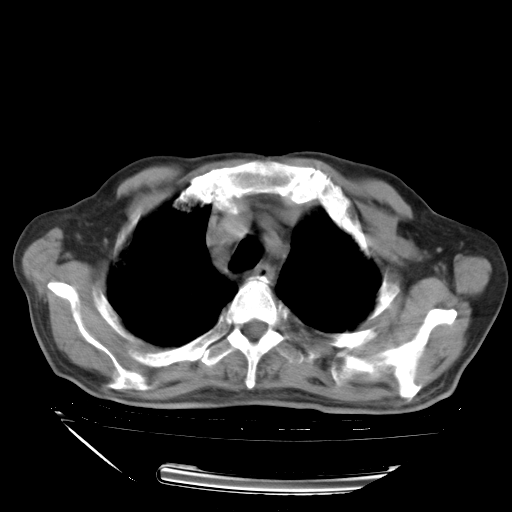

经过24天治疗,岳父的病情基本稳定。生活基本可以自理,可以下床活动。呼吸困难早已消失。体温基本正常。

只是甲强龙用80mg时血小板升到正常,改为60mg后又降到63×10*9/L。

主要治疗甲强龙80mg×14天,60mg×10天;同时抗结核(异烟肼+利福平+乙胺丁醇)。环磷酰胺0.1 tid 10天。

特别感谢胡教授、高管、桃子版主给出关键的治疗建议。桃版把所有肺部影像和全部临床资料请所在医院呼吸科、感染病科、结核科、临床免疫科专家会诊。临床免疫科专家制定了完整的治疗方案。